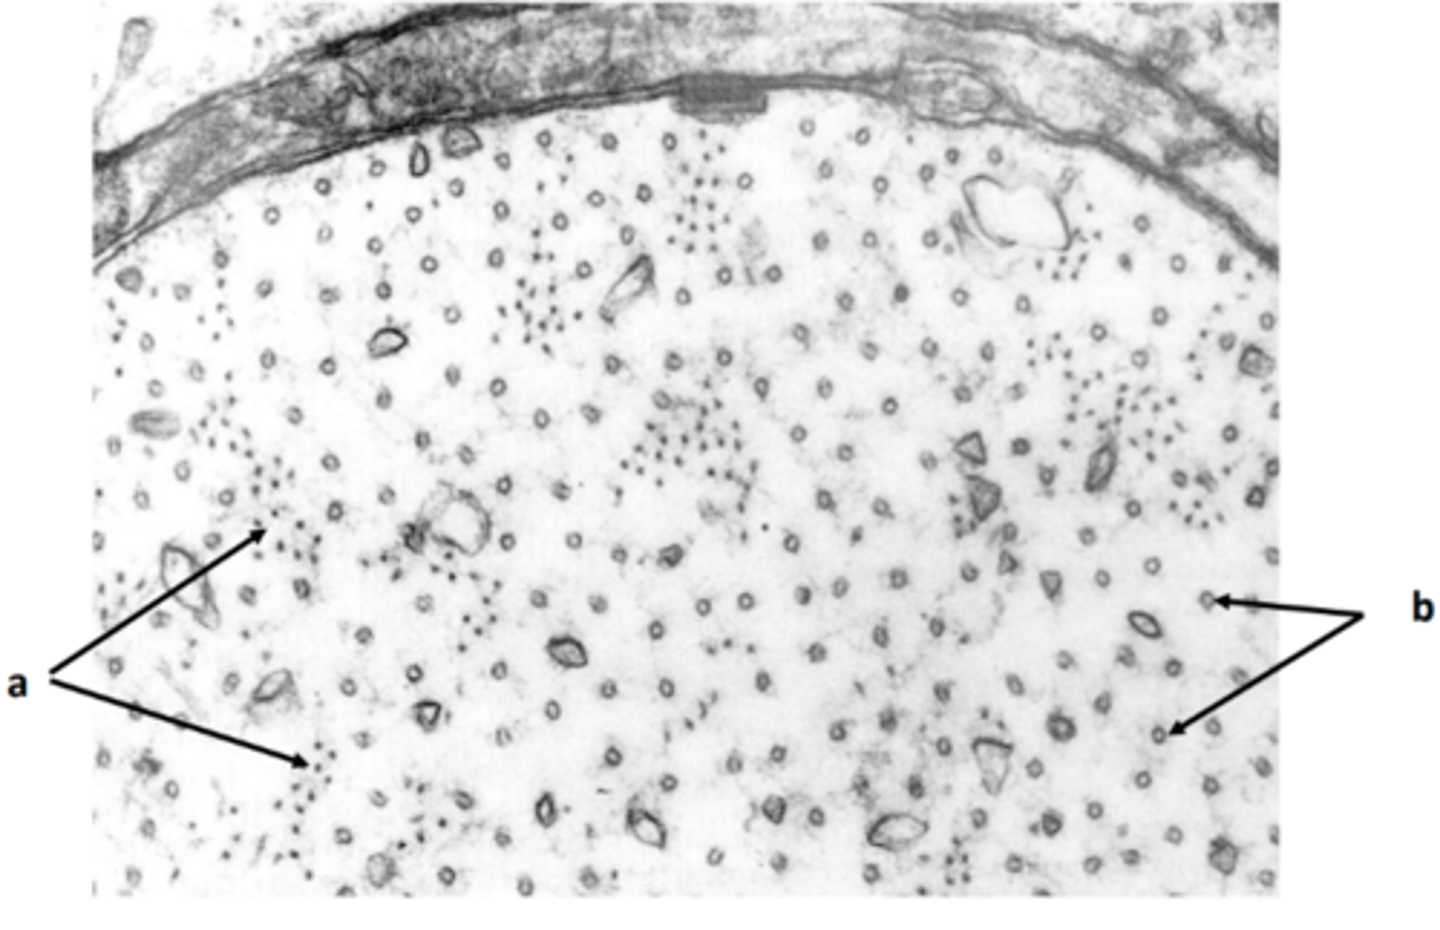

myelin sheath

a: structure

<p>a: structure</p>

9

New cards

schwann cell nucleus

b: structure

<p>b: structure</p>

10

schwann cell cytoplasm

c: structure

<p>c: structure</p>

11

microtubule, neurofilament, mitochondria

d: two structures present in labelled region

<p>d: two structures present in labelled region</p>

neurofilament

22

neurotubule